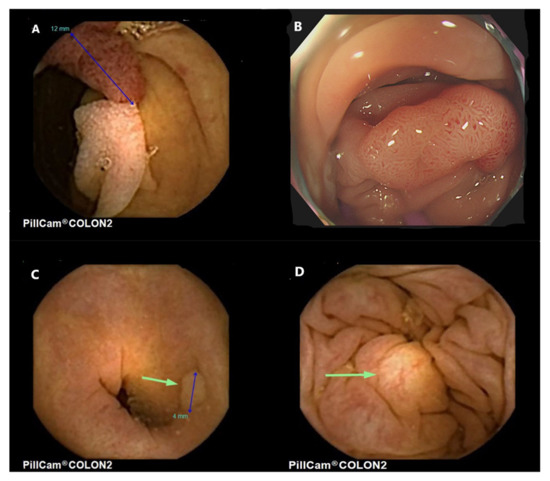

4. CCE-2 and Flat Polyps